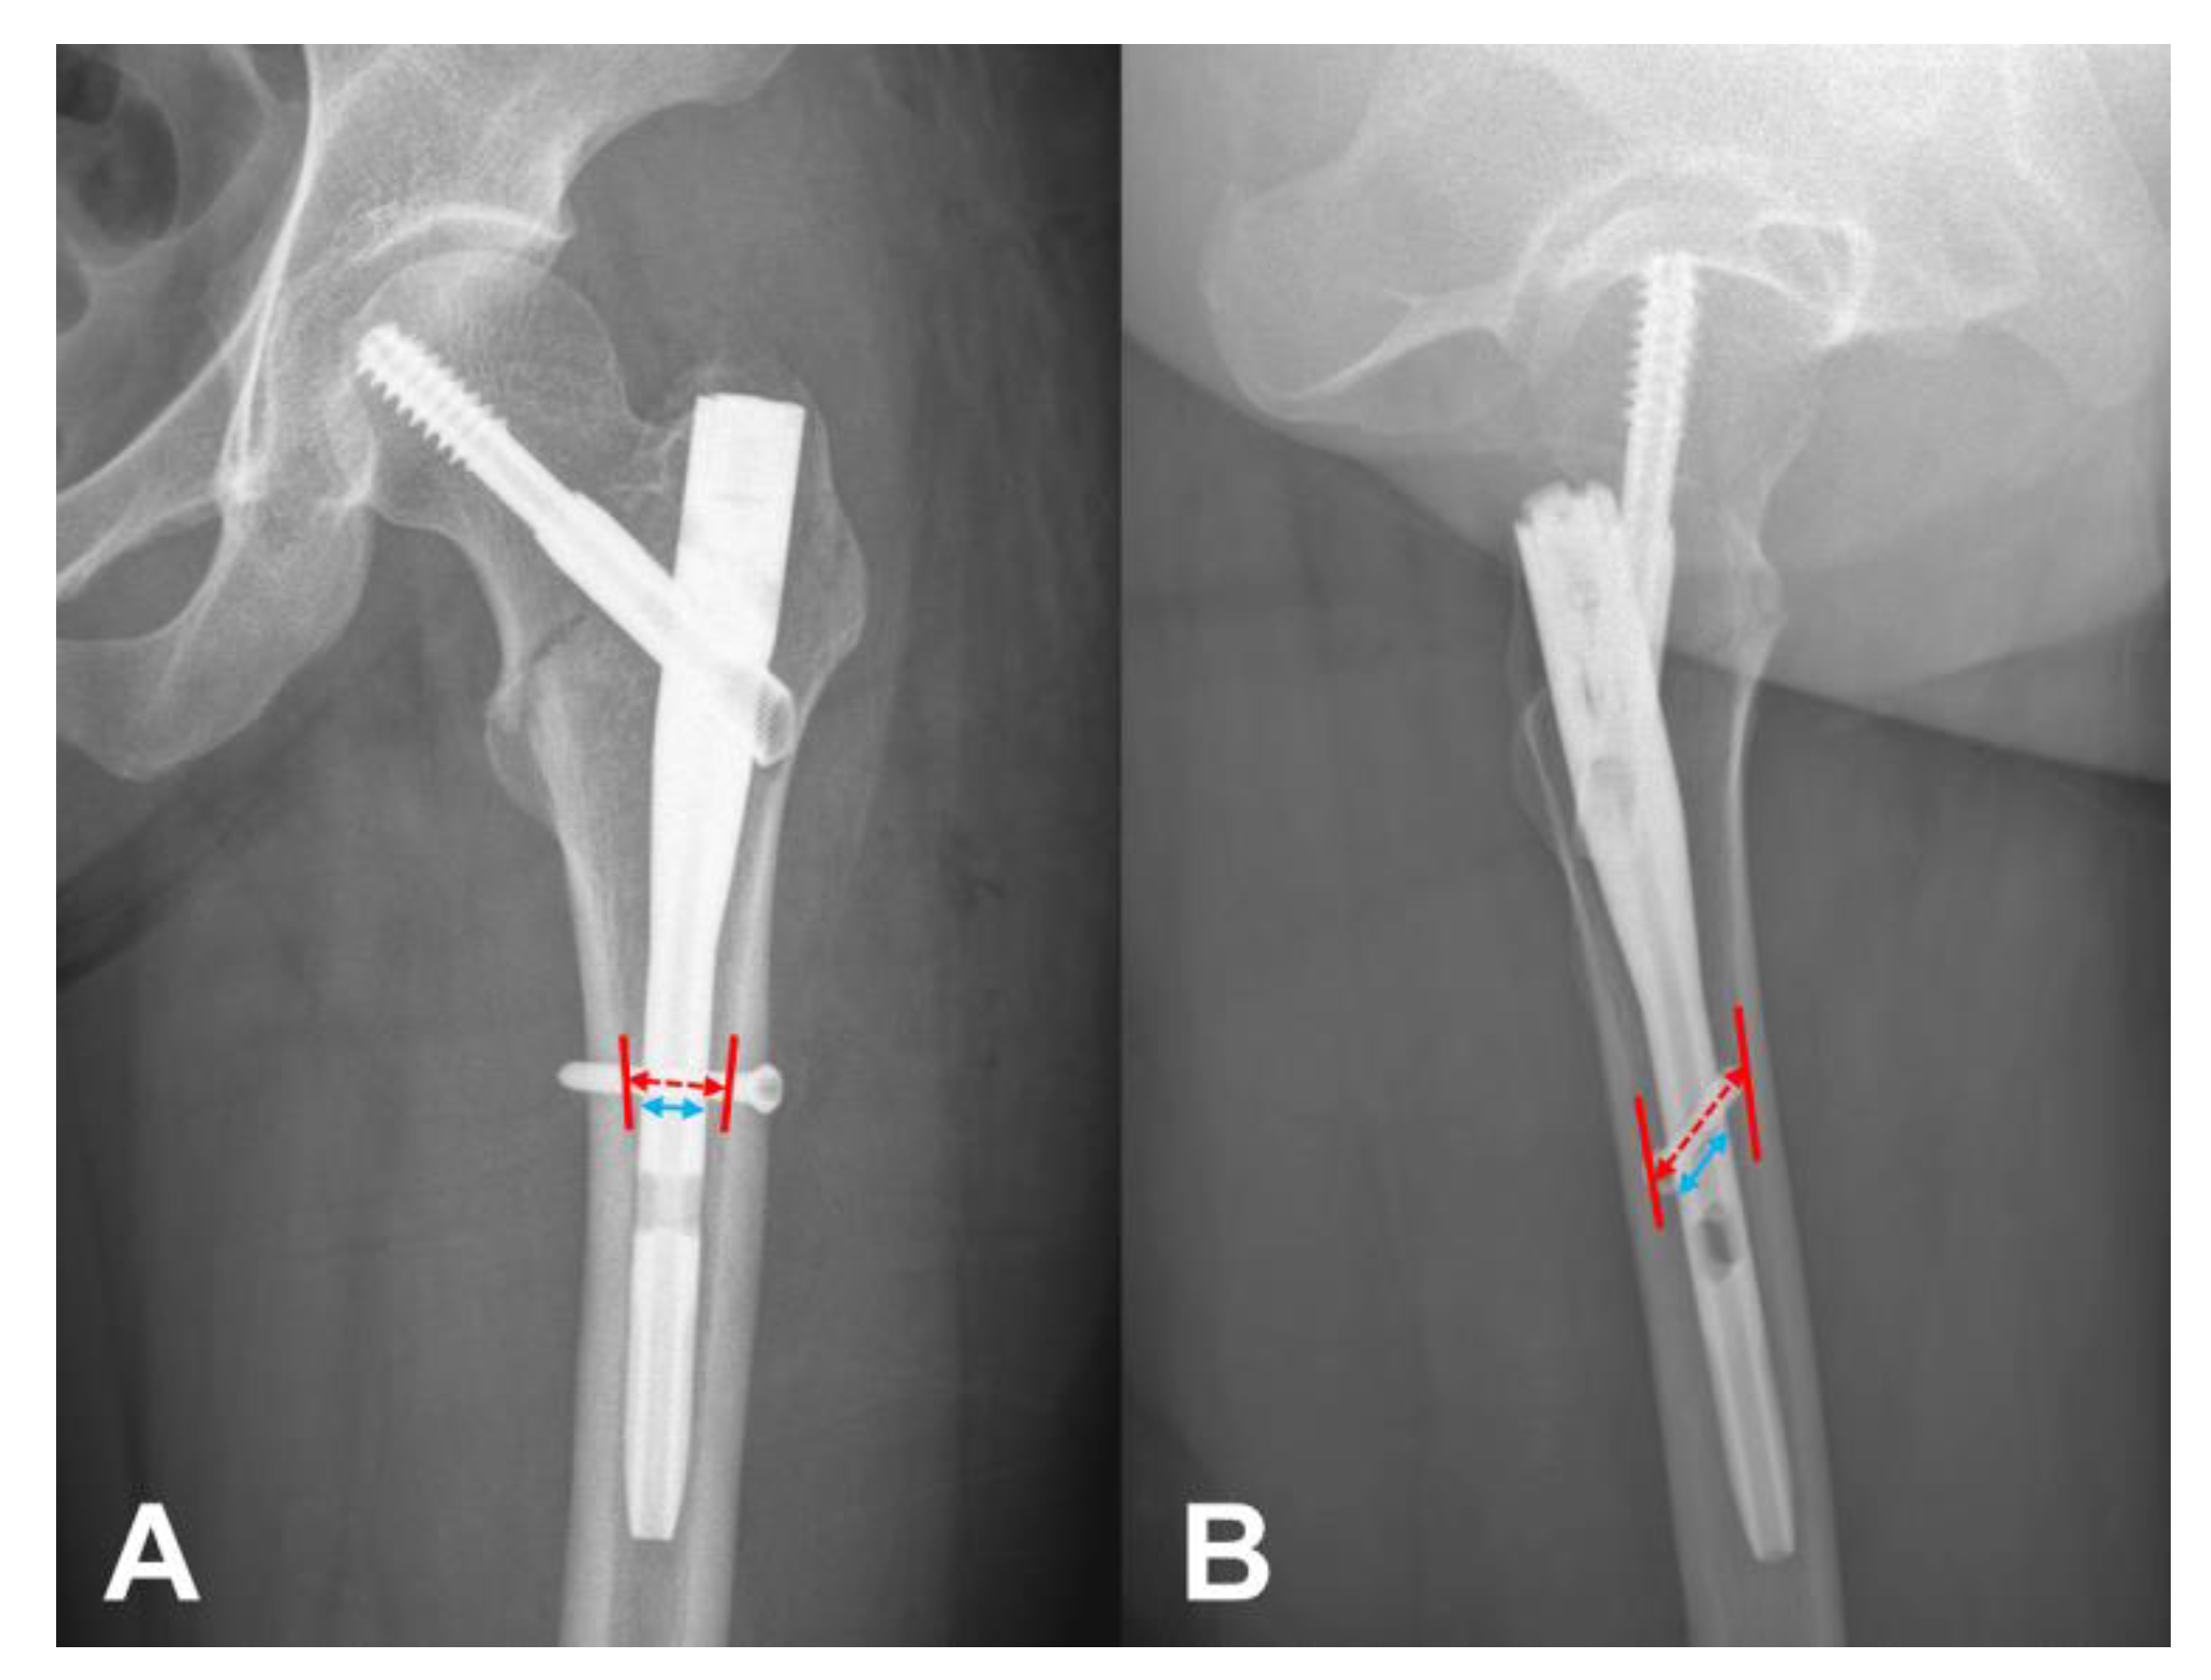

2.1. Measurement of N–C Difference